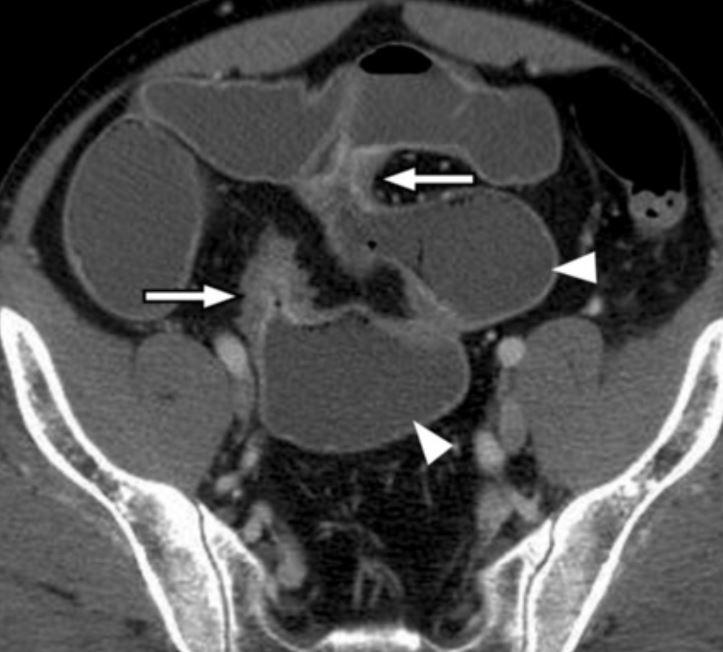

card image

what is this showing in Crohns?

skip lesions

Crohns